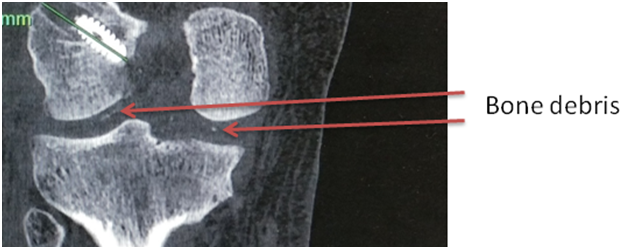

At 9 months patients presented to the clinic with anterior knee pain, restricted range of motion and difficulty in doing squats. On examination bony swelling was present on the medial aspect of the knee, tenderness was present at the donor site and the range of motion was restricted (0-110º). All stability was normal. The arthrometer (KT-1000TM) measurement showed that anterior translation of tibia was 4 mm in the normal knee and 5 mm in the operated knee. X-ray of the knee showed that patellar tendon ossification and heterotrophic calcification at the medial femoral condyle (Figure 1). Patient was managed non-operatively as he did not have any limitation of daily activity.

Figure 1 AP view of x-ray showing heterotrophic ossification on medial femoral condyle and lateral view of left knee x-ray showing patellar tendon ossification.